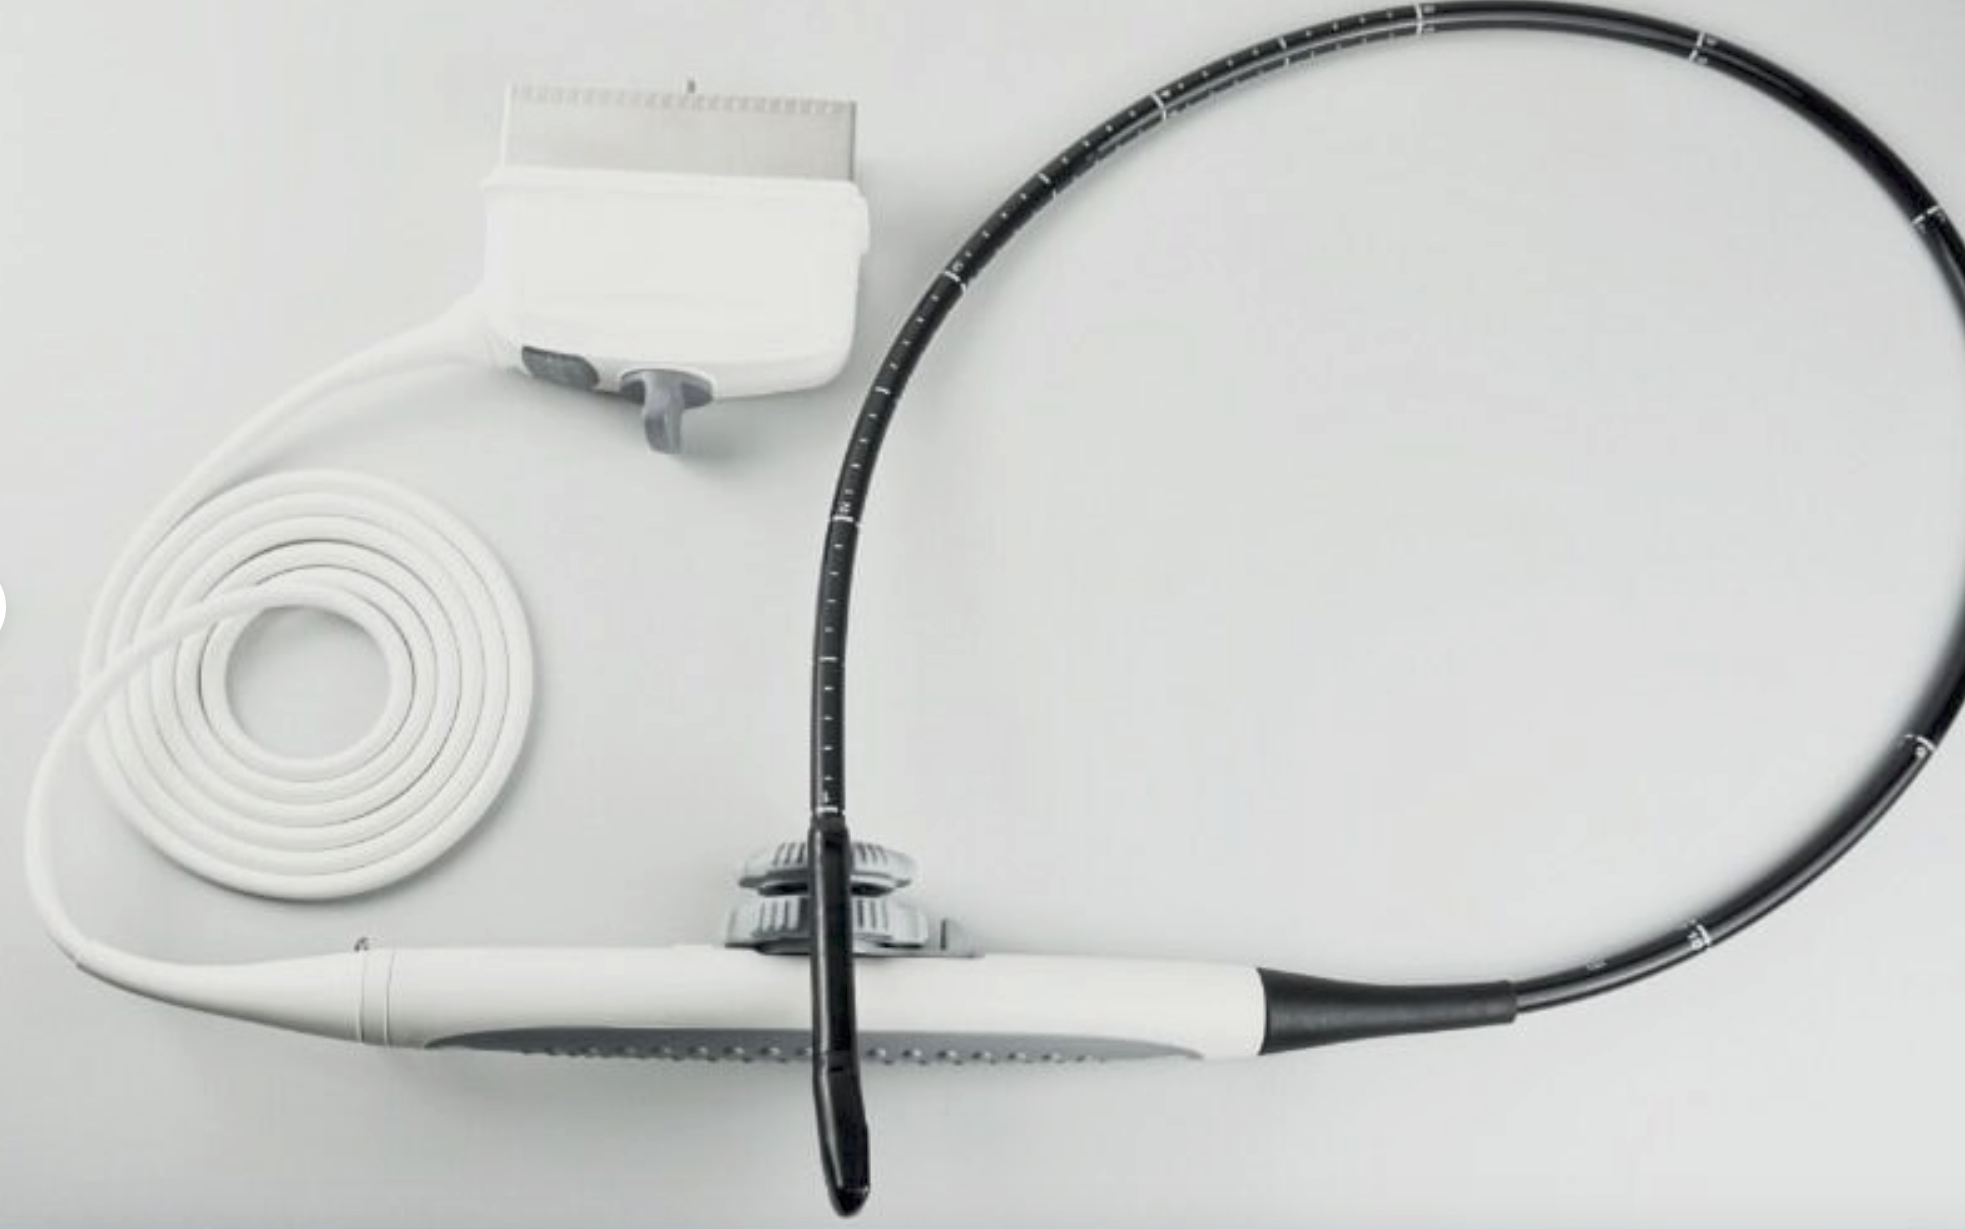

Versatile Probes for Comprehensive Assessment

This system comes with both transvaginal and linear probes, allowing for versatility in patient assessments. For instance, transvaginal probes are particularly useful for gynecological examinations. However, linear probes are ideal for surface-level examinations and vascular assessments. Therefore, having multiple probes enhances the scanner's utility, making it suitable for various medical settings.